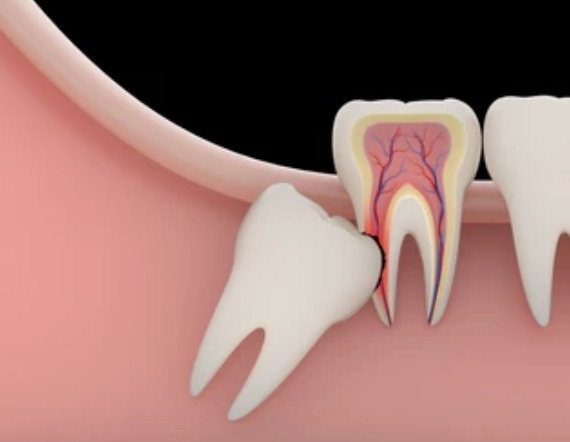

부종이 심할 수밖에 없는

매복 사랑니 발치의 경우에서 자주 나타나요.

사랑니는 일반 치아보다 큰 경우가 많습니다.

게다가 잇몸 깊숙한 곳에 있어요.

큰 치아가 깊숙한 곳에 단단히 박혀있으니,

이런 치아를 뽑아내려면

주변 조직에 자극이 가해질 수밖에 없죠.